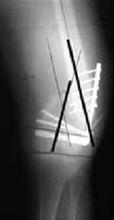

骨不連X線圖片在確定骨不連的治療時,必須考慮以下因素:明確原因,骨不連的部位(具體的骨及骨內的位置),骨 不連的類型,之前的治療,X線表現,以及一系列其他病人的具體特點。在廣義上,治療計畫應包括改善局部生物學行為或/和加強其機械穩定性。常用的改善局部生物性狀的治療方法包括:去除感染灶,骨移植,骨髓移植和套用Ilizarov方法。提高機械穩定性的方法包括:鋼板螺釘內固定術,髓內釘內固定和外固定架。